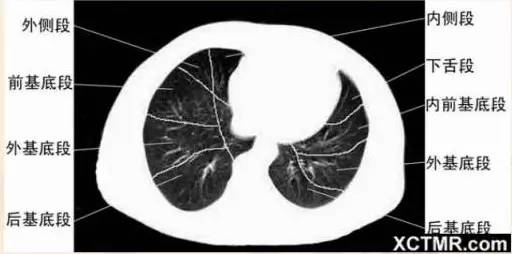

右基底支气管层面